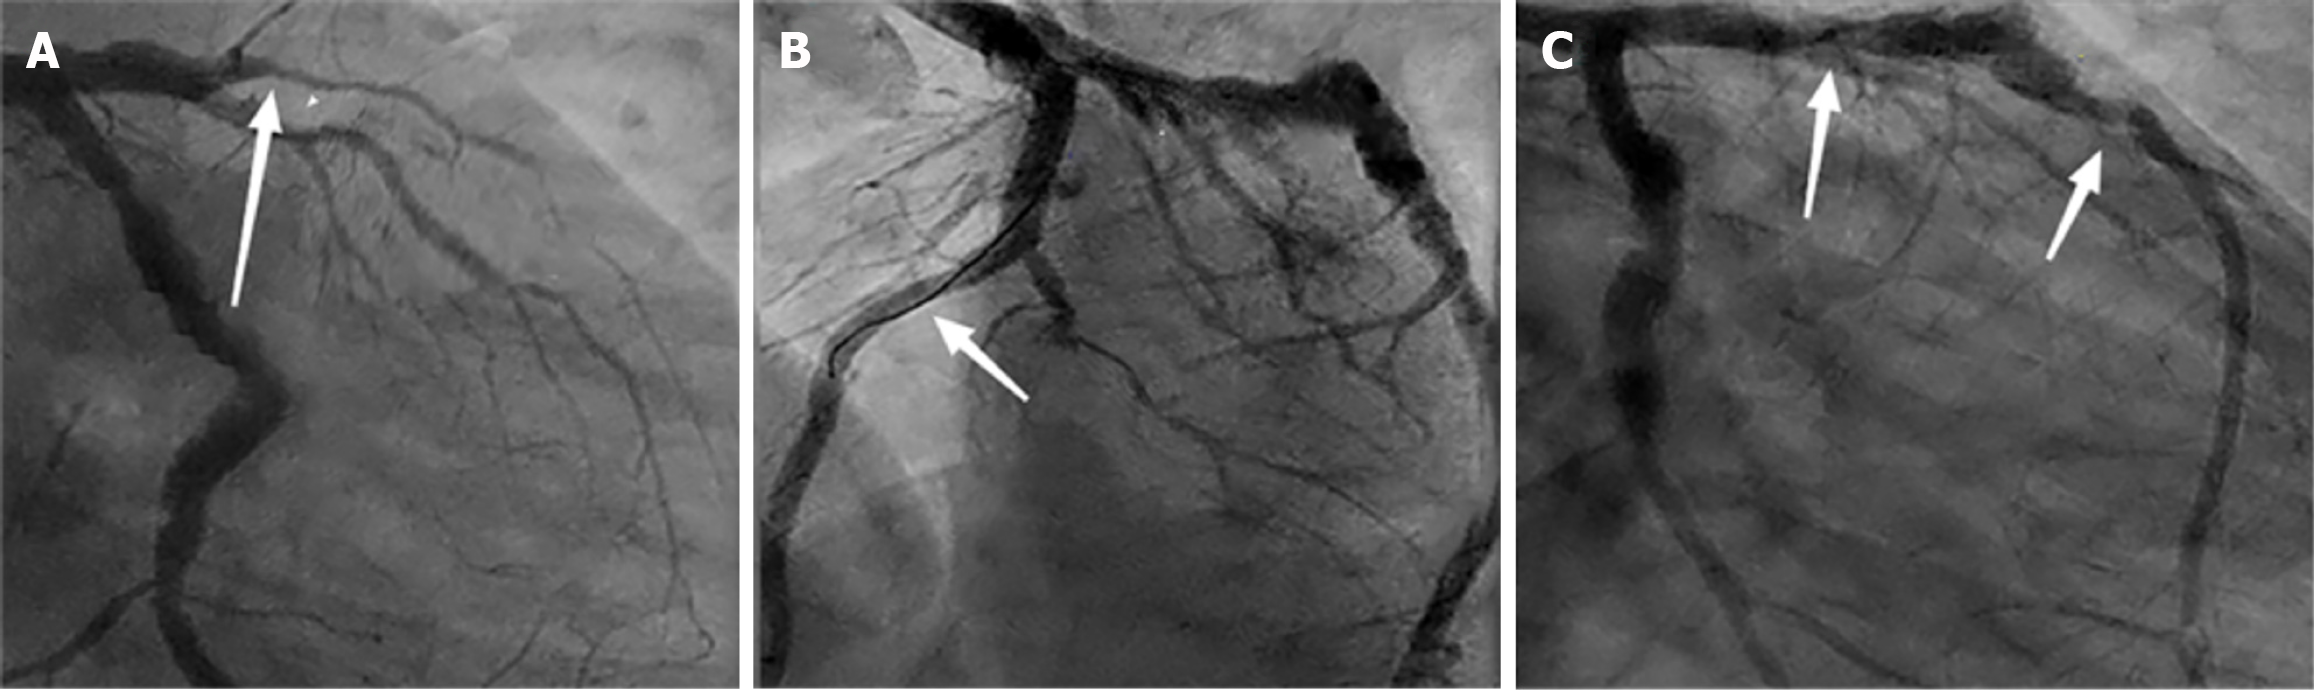

Eighteen cases (33%) in the observation group underwent re-examination by coronary angiography. Regarding adverse reactions, no significant short-term adverse reactions were observed in both groups. During the one-year follow-up period, one patient with an implanted BRS was found to have stent collapse during coronary angiography, with imaging showing discontinuous blood flow and incomplete lesion coverage in the anterior descending branch, partially showing tumor-like dilation (Figure 2). The patient had no obvious clinical symptoms and therefore did not receive treatment but was advised to undergo regular follow-up examinations. Another patient experienced chronic coronary artery occlusion in multiple vessels during the three years after BRS implantation, and underwent coronary artery bypass graft surgery.

BRS patients experience more DoCE events before the 1-year follow-up, which may be related to early healing of the scaffold or thrombosis, reflecting short-term risks. However, these early events are usually manageable through appropriate interventions and do not necessarily affect the final long-term outcomes. The occurrence of late events suggests that, despite higher early risks, the final event rates in BRS patients are similar to those in DES patients as the scaffold heals and remodeling occurs, indicating long-term stability. Therefore, early complications reflect short-term risks of the scaffold, while late events indicate its long-term healing and stability, with both factors ultimately determining the final treatment outcome. From the follow-up angiography results, we observed one case of premature degradation and collapse of the stent, which has been reported in previous studies[25]. This case involved a 46-year-old patient who presented to the emergency department with acute ST-elevation myocardial infarction. Coronary angiography revealed complete occlusion of the mid left anterior descending artery. After balloon pre-dilation, two BRS were successfully implanted. The patient underwent re-examination at one-year follow-up. During the follow-up coronary angiography, we observed an aneurysm-like dilation in the mid segment of the anterior descending artery, along with narrowing at the site of the stent, indicating premature degradation and collapse of the stent. The degradation process was not uniform along the entire length of the stent and was associated with stent discontinuity and incomplete lesion coverage. The exact mechanism leading to premature degradation and stent discontinuity remains unclear. However, this case highlights the potential risks of BRS in the treatment of acute ST-elevation myocardial infarction and further research is needed to confirm these findings.